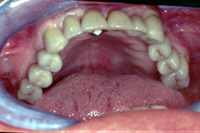

Abb. 7 - Oberkiefer vor der Sanierung.

Abb. 8 - Oberkiefer nach der Sanierung.